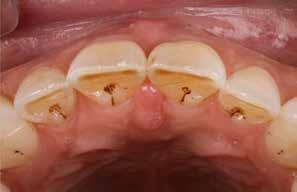

Den kliniske undersøgelse viser harmoniske ekstraorale sagittale forhold med skeletalt dybt bid (Fig. 1A, D). Hendes smil er alderssvarende med en eksponering på 8/10 af overkæbeincisiverne, mens smilets bredde er smalt med synlige mørke laterale rum (Fig. 1D). Underkæbeincisiverne er synlige under tale. Der ses neutrale okklusale forhold ved hjørnetænderne og neutrale pladsforhold i overkæben, men udtalt trangstilling i underkæben især lokaliseret i regio 1-1 (Fig. 1C).

Sliddet klassificeres som grad 2 (moderat tandslid) på de centrale incisiver i overkæbe og underkæbe. Det kan anses som patologisk, da det er atypisk for patientens alder, giver anledning til smerte/ubehag, og giver patienten et æstetisk problem. Der ses infraktioner af overkæbeincisiverne. Der ses endvidere en udtalt Spee-kurve i underkæben og ingen interincisal afstøtning på 2-2 med let ganepåbidning.

Røntgenanalyse viser fravær af -6 samt et velholdt tandsæt uden tegn på sygdom. Profilrøntgenbilledet viser et skeletalt

dybt bid, men normal inklination af fortænder i over- og underkæbe (Fig. 1B).